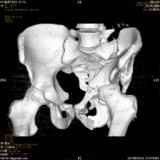

Уважаемые коллеги! Хотелось бы услышать совет по тактике лечения представлленого больного.Поступил после лечения в одном изотделений области. Травма 2,5 месяца назад. После выведенияиз шока был произведен остеосинтез перелома бедра, предплечья, до перевода к нам проводилосьвытяжение по оси шейки бедра за стержень, введенный в большой вертел. На сегодня деформацияригидна, клинически мобильности не определяется. Заранее признателен. P.S. Данный вид травм не включен в перечень "высокотехнологичных операций", направить длялечения по квотам Минздрава очень сложно.

Это обзорные и косые снимки

Привет, Леонид. Оскольчатый высокий двухколонный перелом в такие сроки трогать не надо, т.к. это про такие переломы сказано: "кто с ножом на Ж. пойдет тот в ней и останется...".